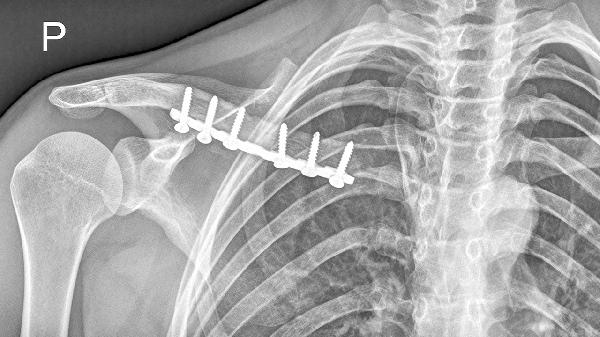

骨折线模糊是开始锻炼的基础指标,需通过X光确认骨痂形成。临床愈合通常需3-4周,此时可进行被动关节活动。完全负重训练需等待骨性愈合,约需8-12周。

合并臂丛神经损伤需延迟至6周后锻炼。出现反射性交感神经营养不良时,应优先进行疼痛管理。二次移位风险高的粉碎性骨折需延长固定时间2-3周。